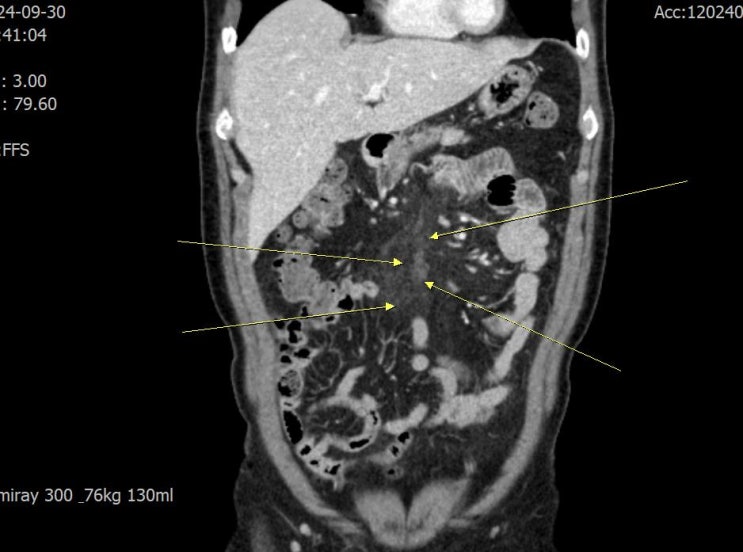

Bacteria somewhere, bacteria nowhere, bacteria in mesentery?(세균이 어디 있는데, 아무 데도 안 보이면, 장간막에 있는가?)

이분은 병원에 오기 3일 전에도 골프도 치고 짐(gym)에 가서 상당히 과격한 운동을 하고 나서, 등과 팔이 ...